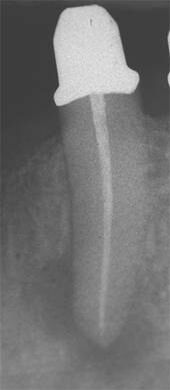

Schmerzhafter Zahn mit röntgenologisch eindeutiger Entzündung im Knochen (periapikale Aufhellung). -